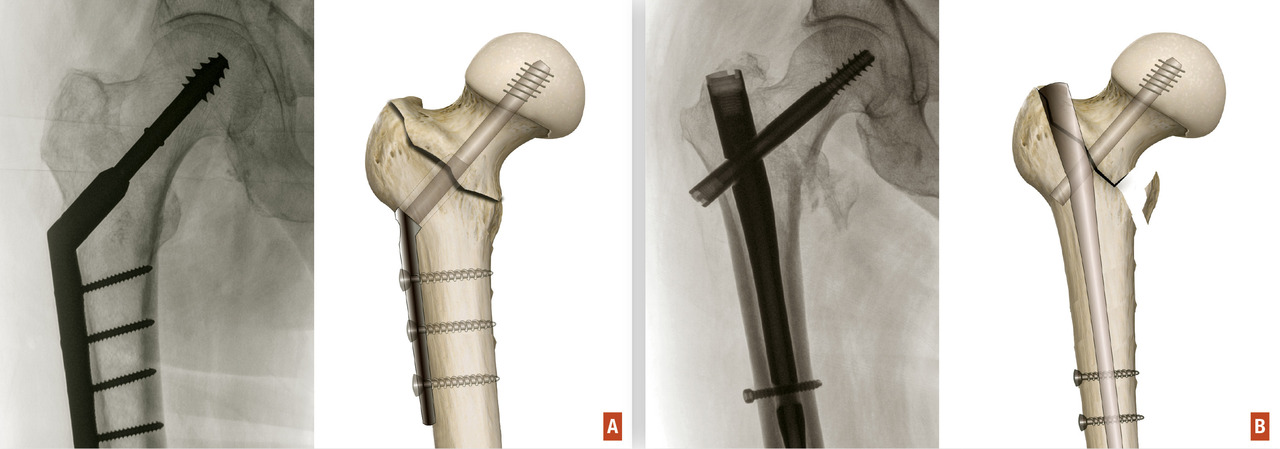

En cas de fracture du massif trochantérien, compte tenu du faible risque de nécrose, la solution chirurgicale est presque toujours l’ostéosynthèse. Cette dernière a pour but de fixer la fracture une fois la réduction de celle-ci obtenue. Il peut s’agir d’une vis-plaque ou d’un clou fémoral proximal verrouillé type clou gamma (fig. 15). Dans les cas de fracture particulièrement instable ou lorsque la fracture s’étend vers la diaphyse, l’ostéosynthèse par clou est recommandée.